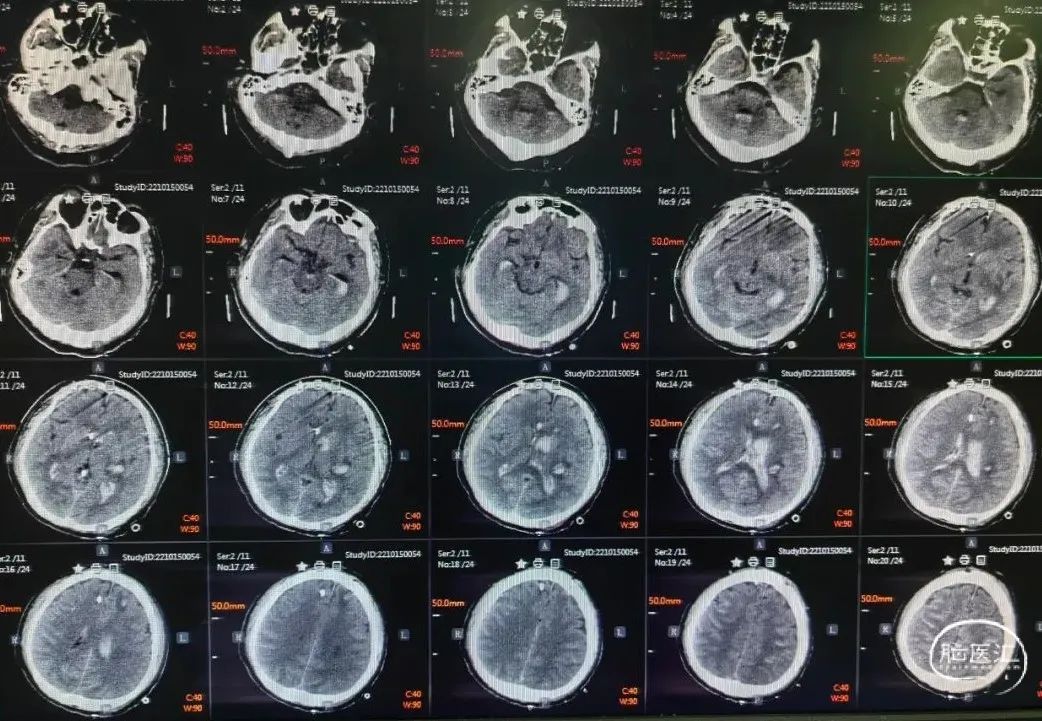

术前CT提示:脑内血肿,蛛网膜下腔出血。

术后第1天头颅CT提示:脑室系统积血较多,安排床旁锥颅脑室钻孔引流,尿激酶液化血肿。

术后一周头颅CT提示:脑室系统积血较前明显减少,更换腰大池置管引流。